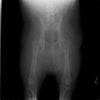

術後側面像

術後正面像

術前に25°であったTPAは、TPLO実施により7°に矯正されました。症例の歩行状態は良好です。